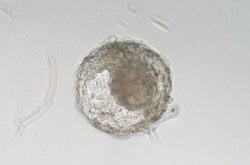

Araştırmacılar, fare veya insan kök hücrelerinden çeşitli embriyo stand-in'leri uydurdular. Çin'deki bilim insanları ilk maymun versiyonlarını yarattılar. İnsan embriyo taklitlerinden farklı olarak, bilim insanlarının hamileliğin başlangıcını ve neden genellikle başarısız olduğunu daha iyi anlamalarına yardımcı olmak için dişilere yerleştirilebilirler.